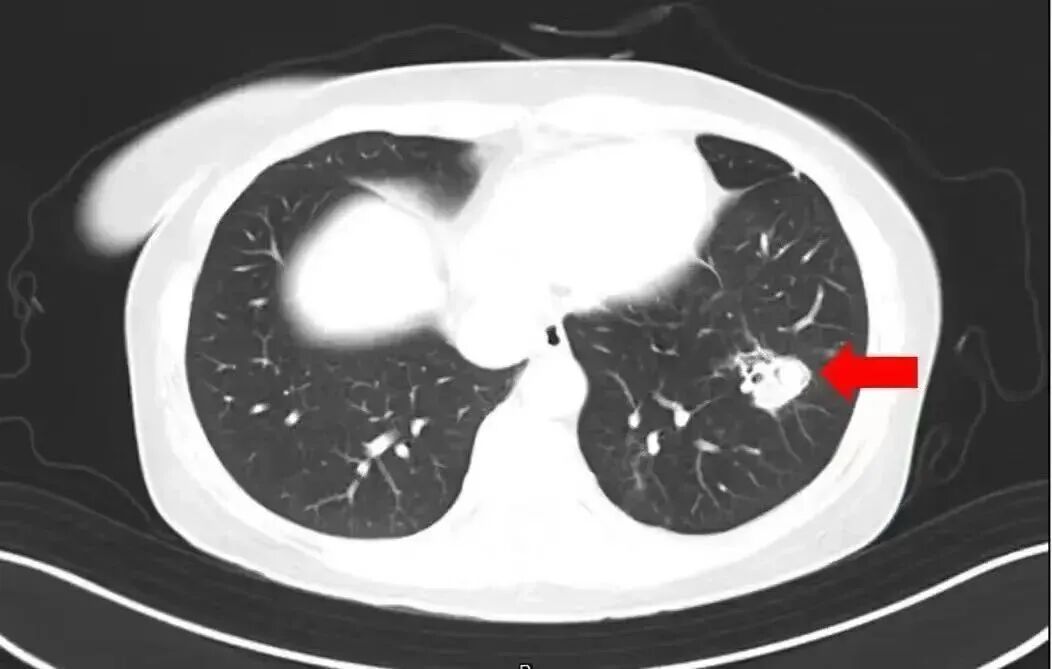

近日,有一条新闻引发网友关注:河南郑州一名6岁女孩跟随家人对老家房子进行清扫,随后就开始持续发烧。经医院检查,发现其脑部被真菌侵蚀出很多个“空洞”。罪魁祸首,就是老房子里霉变粉尘中的“烟曲霉”。

2025年1月,江苏扬州的张大爷为迎接春节开始大扫除,清扫过程中不慎吸入大量灰尘和霉菌孢子,导致哮喘发作。张大爷随即服用了常备的哮喘治疗药物,可症状反而逐渐加重。经检查,张大爷的肺部出现感染,确诊为肺曲霉病。

北京佑安医院感染综合科主任医师李侗曾介绍,对于免疫力低下的人,吸入了这些真菌,就会发病引起肺部的病变——曲霉肺炎。因为它是通过呼吸道感染的,进入血液后是可以扩散到全身。大脑因为血供最丰富,所以也是真菌最容易侵犯的器官。